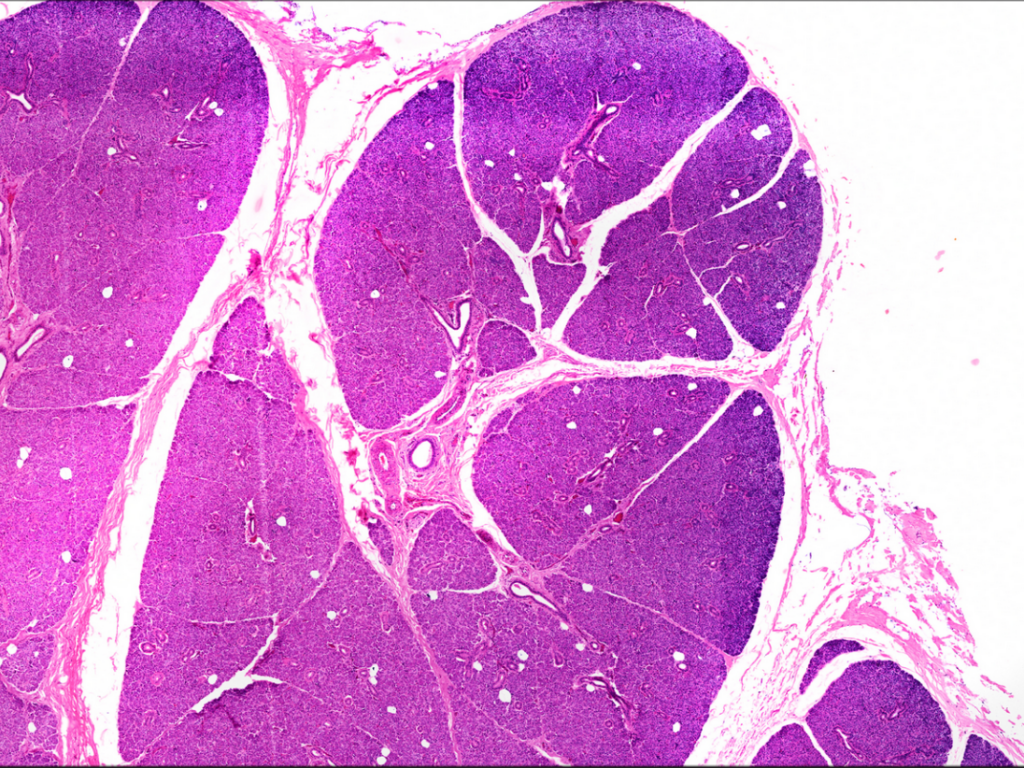

- Torebka, przegrody i płaciki (ślinianka przyuszna)